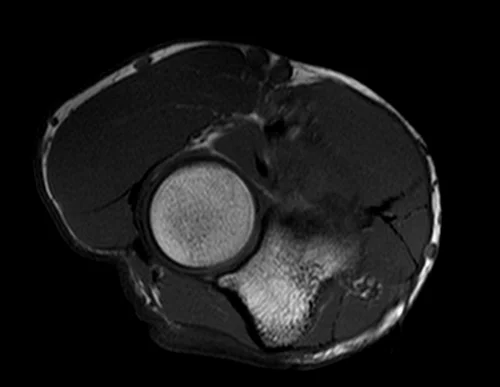

mri elbow axial t1 image 2 - MRI